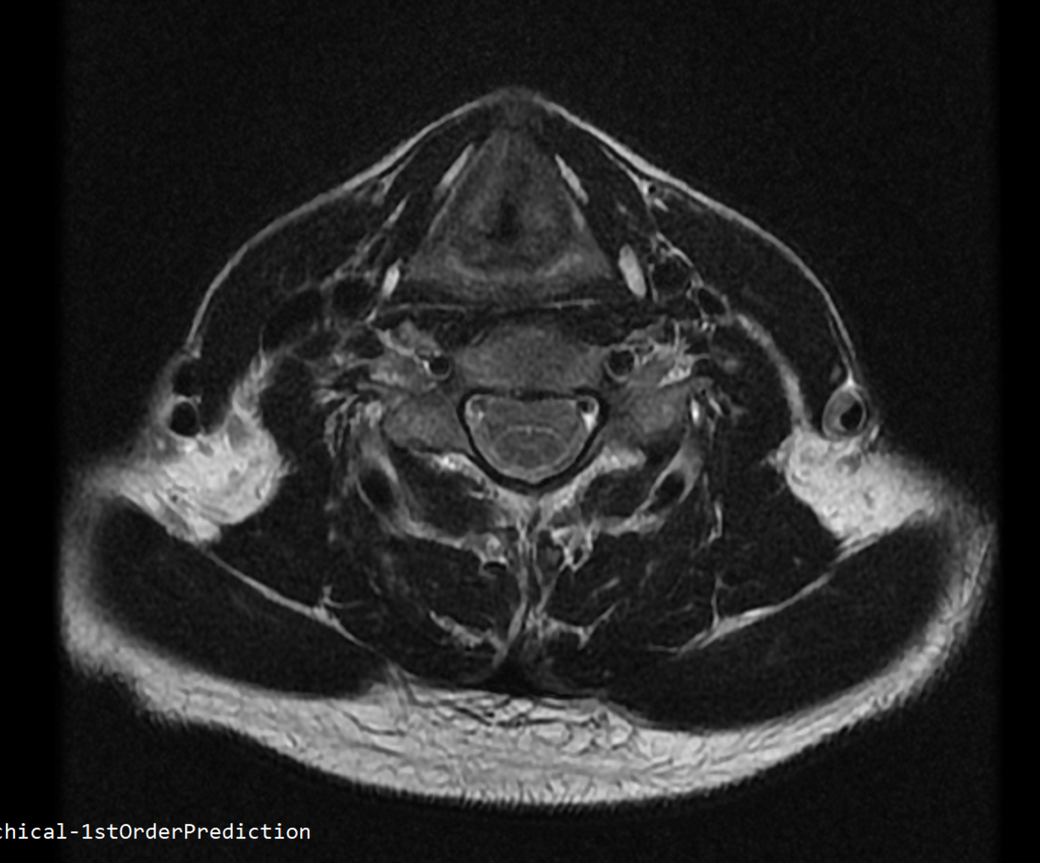

안녕하세요 목 경추 상단부터 순서대로 mri 촬영인데요

전체적으로 봐주시면 감사하겠습니다

• 1번 째 사진